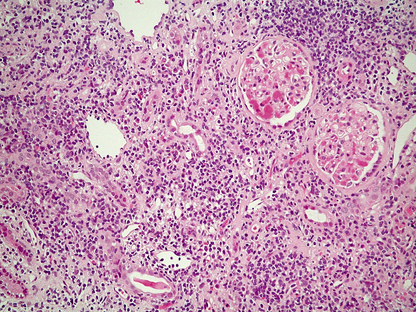

Histological features

The glomeruli are distended and hypercellular (Fig. 21.6A). All of the glomeruli are involved, hence the use of the term ‘diffuse’. The increase in cellularity is due to the proliferation and swelling of mesangial, endothelial and epithelial cells, together with polymorphonuclear leukocytes. Some glomeruli may show proliferation of cells lining Bowman’s capsule to form a crescent; the presence of crescents in 60% or more of the glomeruli indicates a rapidly progressive disease and heralds a poor prognosis. There is usually interstitial oedema and a variable inflammatory cell infiltrate. The tubules contain red cell casts and the tubular epithelial cells may show degenerative changes.

image

Fig. 21.6 Diffuse proliferative glomerulonephritis. image The glomerular injury in this case, characterised by hypercellularity owing to cellular proliferation and acute inflammatory cell infiltration, is due to immune complex deposition. image Ultrastructure of diffuse proliferative glomerulonephritis. The principal abnormality is the presence of electron-dense immune complexes deposited between the epithelial cells and the basement membrane. The cells with the granular cytoplasm in the lumen are neutrophil polymorphs attracted by the activation of complement in the loose subendothelial material.

Using immunofluorescence techniques, granular deposits of IgG and C3 are identified on the peripheral basement membranes. Ultrastructurally, subepithelial deposits correspond to the granular IgG and C3 demonstrated by the immunological techniques (Fig. 21.6B).